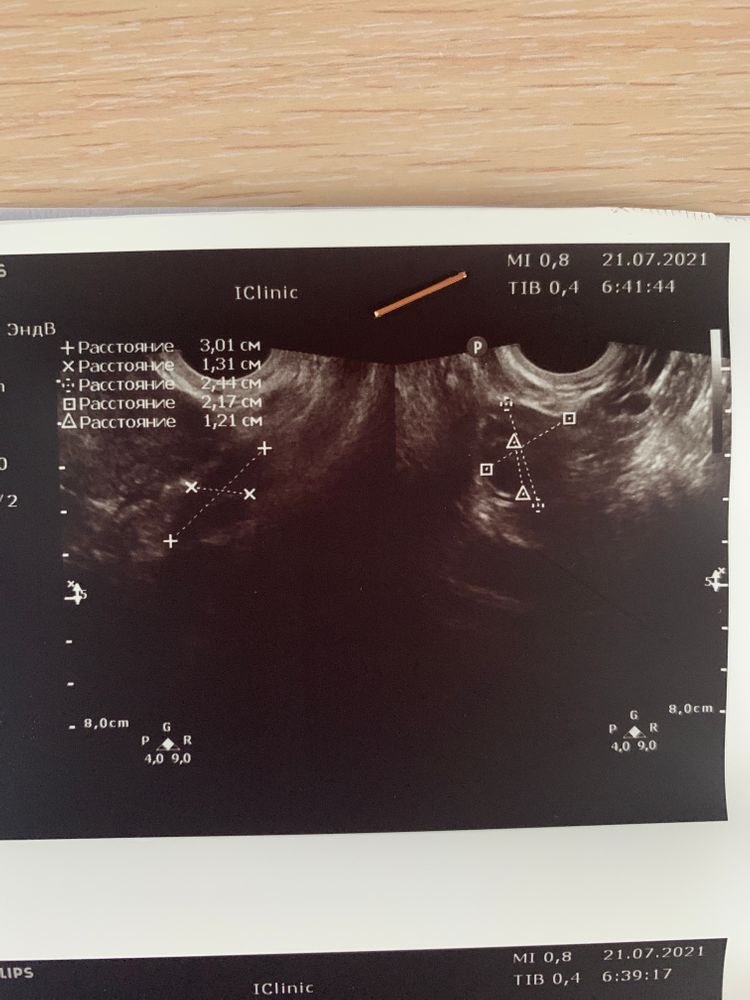

сделали узи, сказала была овуляция

в заключении сказано «со стигмами овуляции»

желтое тело